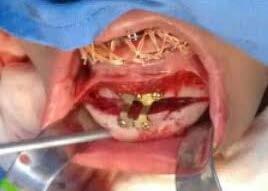

Segunda fase quirúrgica de impactación maxilar Lefort I, 4 mm, (Figura 7), se realizó la cirugía mandibular que consistió en la osteotomía sagital de la rama bilateral de avance, 9 mm (Figura 8), se hizo la cirugía del mentón con la mentoplastía de avance 4 mm, (Figura 9) y una fase postquirúrgica de detallado y retención.

Fueron realizados después de 1 año y 2 meses de haber iniciado el tratamiento y después de la cirugía. En los estudios radiológicos tenemos que en la radiografía lateral de cráneo las placas utilizadas para consolidar la fijación de los maxilares, la corrección de las relaciones esqueléticas en la Figura 10. En la panorámica inicial se señalan los gérmenes de los terceros molares (Figura 11) y en la Figura 12, la realización de las exodoncias de órganos dentarios 18, 28, 38 y 48.

En los estudios intraorales de progreso en la fotografía de frente se observa la mejoría el overjet y overbite (Figura 13), así como la coincidencia de las líneas medias dentarias. Se obtuvo las relaciones clases I caninas y molares para la obtención de la máxima intercuspidación, y para el paralelismo radicular se utilizaron arcos de acero, así como la oclusión funcional, con el detallado rectangular 0.019 × 0.025 superior e inferior, dobleces de primer, segundo y tercer orden y elásticos en W.